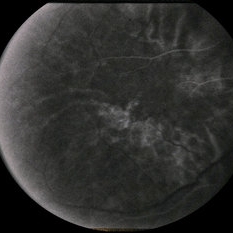

---thumb.jpg/image-square;max$300,300.ImageHandler) Age Related Macular Degeneration - Geographic Atrophy

Age Related Macular Degeneration - Geographic Atrophy

May 3 2013 by Suber S. Huang, MD, MBA, FASRS

Geographic Atrophy.

Imaging device: Retina Diseases Imaging Analysis Reading Center

Condition/keywords: advanced geographic atrophy, atrophic scar, atrophic spot, geographic atrophy, macula lesion, pigment epithelial atrophy